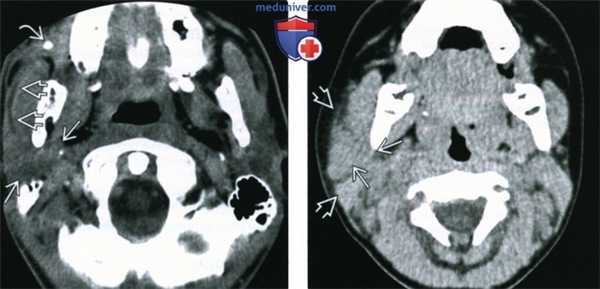

(Слева) КТ с КУ, аксиальная проекция. Подросток с обструктивным паротитом, определяется характерное увеличение правой околоушной железы с накоплением в ней контрастного вещества и расширение протока железы. В дистальном отделе протока обнаружен конкремент.

(Справа) КТ без КУ, аксиальная проекция. Диффузное увеличение правой околоушной железы, возникшее у пациента после травмы. Также имеется отек окружающей жировой клетчатки.

2. КТ при остром паротите:

• КТ без контрастирования

о Бактериальный: увеличенная железа повышенной плотности с нечеткими контурами

о Вирусный: увеличенная железа повышенной плотности

о Обструктивный: обычно удается визуализировать камень в протоке железы

о Аутоиммунный: окружающая жировая клетчатка поражается в меньшей степени

• КТ с КУ:

о Бактериальный: увеличенная железа, равномерно накапливающая контрастное вещество:

- Воспалительная исчерченность жировой клетчатки

- При наличии абсцесса - содержимое пониженной плотности с кольцом накопления контраста

о Вирусный: увеличенная околоушная железа, незначительно накапливающая контрастное вещество о Обструктивный: проток железы увеличен, стенки накапливают контраст, в остальном картина аналогична бактериальному воспалению

о Аутоиммунный: исчерченность жировой клетчатки меньше:

- При длительном процессе возможно расширение протока